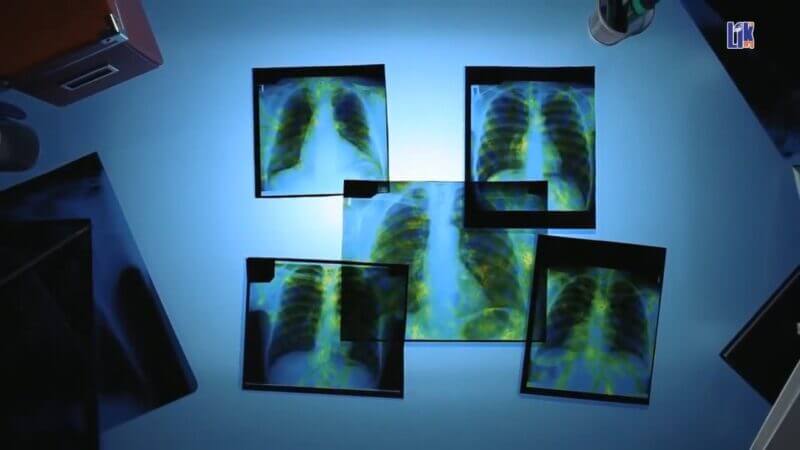

Туберкулёз — проблема общества. Можете ли Вы предположить, что сегодня, в мирное время, от туберкулеза ежедневно умирают 5000 человек? С давних времен туберкулез считается бичом человечества и, несмотря на все современные достижения в медицине, эта болезнь по-прежнему является одной из глобальных проблем современности.